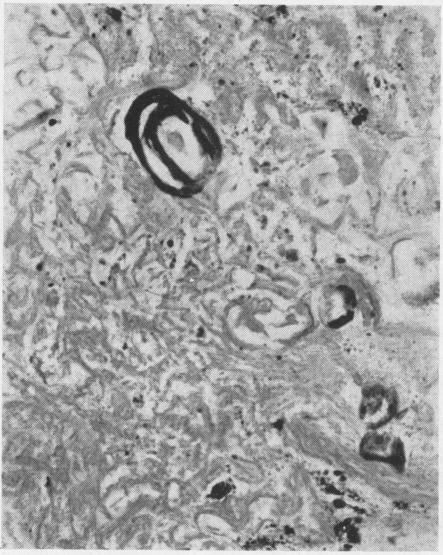

A histological study of the lungs in 52 cases of chronic beryllium disease.

Br J Ind Med. 1958 Apr;15(2):84-91. doi: 10.1136/oem.15.2.84.